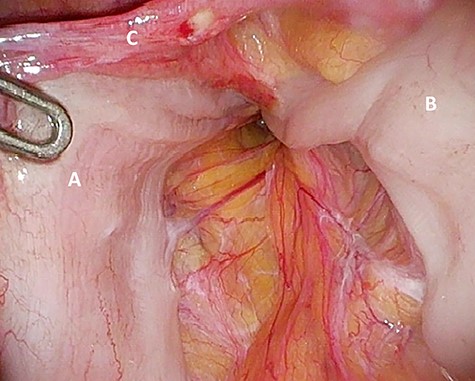

Considering the patients’ comorbidities (obesity, Type 2 diabetes mellitus), a re-TAPP was performed to avoid possible wound complications. The recurrent hernia was presumably confirmed as a lateral inguinal hernia. After dissecting dense fibrotic scar tissue around the previous mesh preperitoneally, the hernia sac was released. A large spermatic cord lipoma was found and dissected (Figs 1 and 2). A new mesh (BARD® 3D Light Mesh, 10 × 15 cm) was inserted.

Dissection of the large spermatic cord lipoma with attached fibrotic tissue.